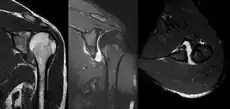

A diagnosis of shoulder dislocation is often suspected based on the person's history and physical examination. Radiographs are made to confirm the diagnosis. Most dislocations are apparent on radiographs showing incongruence of the glenohumeral joint. Posterior dislocations may be hard to detect on standard AP radiographs, but are more readily detected on other views. After reduction, radiographs are usually repeated to confirm successful reduction and to detect bone damage. After repeated shoulder dislocations, an MRI scan may be used to assess soft tissue damage. In regards to recurrent dislocations, the apprehension test (anterior instability) and sulcus sign (inferior instability) are useful methods for determining predisposition to future dislocation.

An anterior dislocation of the shoulder

An anterior dislocation of the shoulder Anterior dislocation of the right shoulder. AP X ray

Anterior dislocation of the right shoulder. AP X ray Anterior dislocation of the right shoulder. Y view X ray.

Anterior dislocation of the right shoulder. Y view X ray.